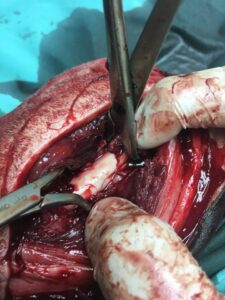

Operationsfotos

Von unserem Patienten (siehe vorletzten Bericht) haben wir hier einige Fotos der erfolgten, erfolgreichen Operation: